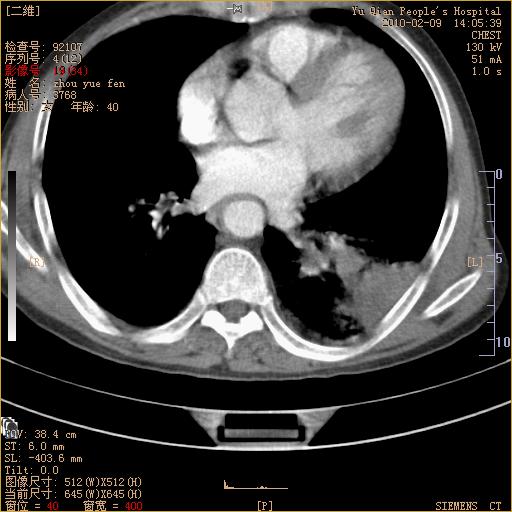

男性,73岁,咳嗽咳血数天,诊为肺ca伴左肺下叶后段阻塞性炎症、肺不张妥否?

左下肺中央型肺癌伴结段形肺不张,左侧胸腔积液,纵隔内见部分增大淋巴结(反应性增生或转移)

左下基底干支气管明显变窄。

左肺下叶基底段支气管狭窄,左肺门增大,左肺下叶团片状病灶。中心型肺癌伴柱塞性炎症可能大,建议支气管镜检查。

左下肺中央型肺癌伴节段性肺不张,左侧胸腔积液,纵隔内见肿大淋巴结

左下基底段支气管变窄。建议进一步纤支镜检查。

1、左肺下叶后基地段肺癌伴阻塞性炎症,左下肺门淋巴结转移。2、左侧胸腔积液。